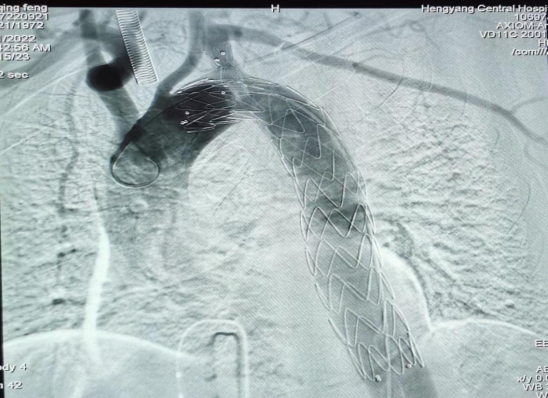

疾病的兇險與手術(shù)費的昂貴,讓許先生一家人左右為難。了解許先生經(jīng)濟困難,心血管中心趙慶禧主任醫(yī)師與患者充分溝通后,決定放棄傳統(tǒng)的穿刺方法(需使用血管縫合器),行股動脈和左側(cè)肱動脈切開入路,既保證了手術(shù)安全性又兼顧了經(jīng)濟性。最終在9月21日,許先生愿意接受介入微創(chuàng)治療。趙慶禧帶領(lǐng)介入團隊和麻醉科團隊密切配合,為其施行全麻下行“Castor分類型覆膜支架植入術(shù)”。僅在患者的左肱動脈,右股總動脈處分別做不到1cm的小切口,然后在DSA引導(dǎo)下精確定位,釋放覆膜支架一枚,保住鎖骨下動脈的同時也堵住了主動脈內(nèi)膜破口,手術(shù)歷時三個小時,順利完成,“致命炸彈”被徹底拆除,術(shù)后許先生恢復(fù)良好,于住院的第30天順利出院。

(術(shù)中釋放的一體式覆膜支架)